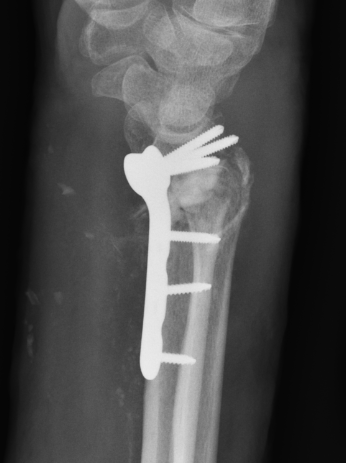

Undisplaced wrist fracture

- interrupts blood supply at a watershed area

- between 3 weeks and 3 months post injry